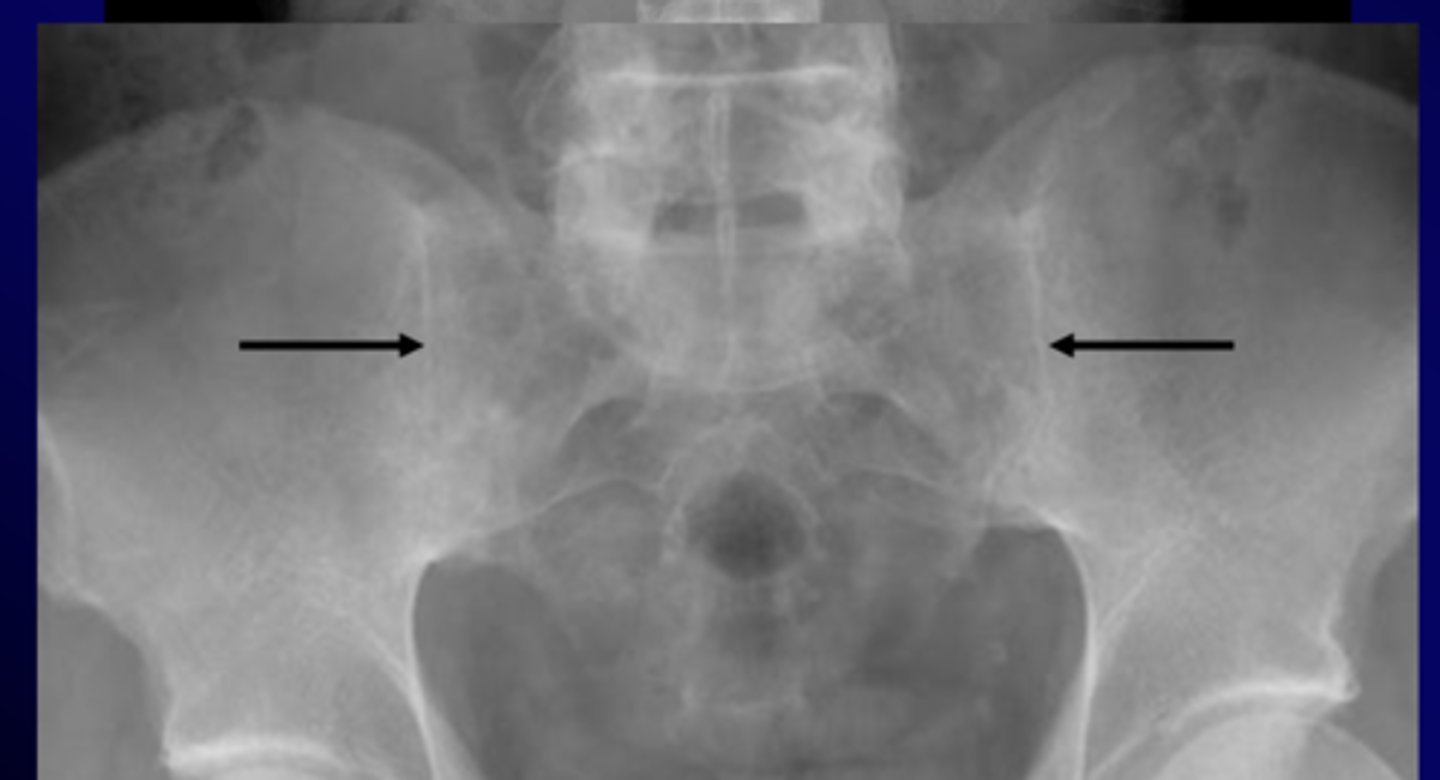

ankylosing spondylitis

chronic and progressive arthritis characterized by inflammation and eventual fusion of sacroiliac and spinal facet joints, involvement of paravertebral soft tissues, more common in young males

xray

- sacroiliitis: bony fusion or ankylosis of sacrum and ilium